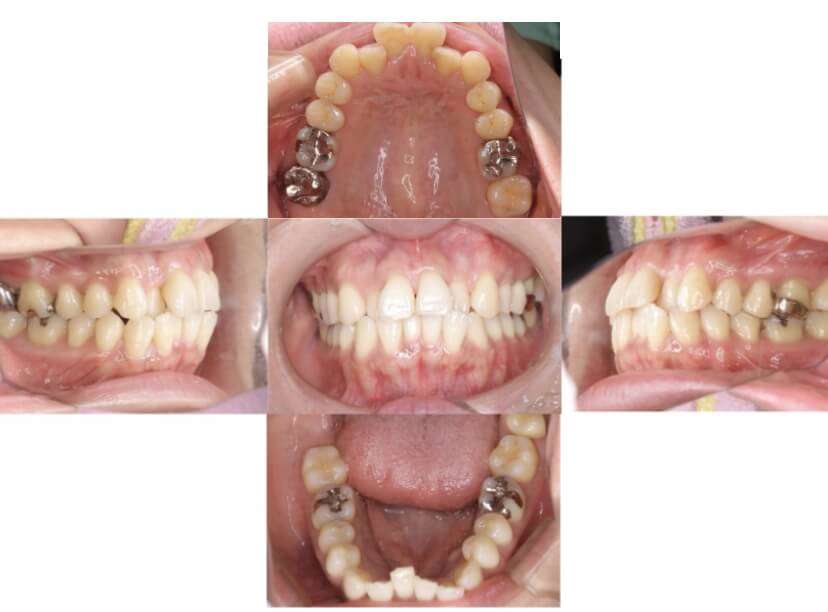

症例1

上顎前突、叢生

抜歯

ブラケット矯正

上下顎叢生、上顎前突(出っ歯、上下の前歯のガタガタ)のケースです。

装置はラビアル(上下表側)で、上顎の小臼歯を2本抜歯を行っています。抜歯したスペースを使って、上の前歯の後方移動と叢生(ガタガタ)と出っ歯の改善を行っています。下は歯と歯の間にIPR(隣接面削合)を行い、スペースを確保し、叢生の改善を行っています。

主訴 前歯のガタガタと出っ歯が気になる。

年齢・性別 47歳 女性

お住まいの地域 神奈川県川崎市

治療方針 抜歯スペースおよびIPRを利用して上前歯の叢生(ガタガタ)の改善

抜歯部位 上顎左右第一小臼歯

使用装置 ラビアル(上下表側)、顎間ゴム

治療期間 2年0か月

治療回数 15回

リテーナー クリアリテーナー

BEFORE

AFTER